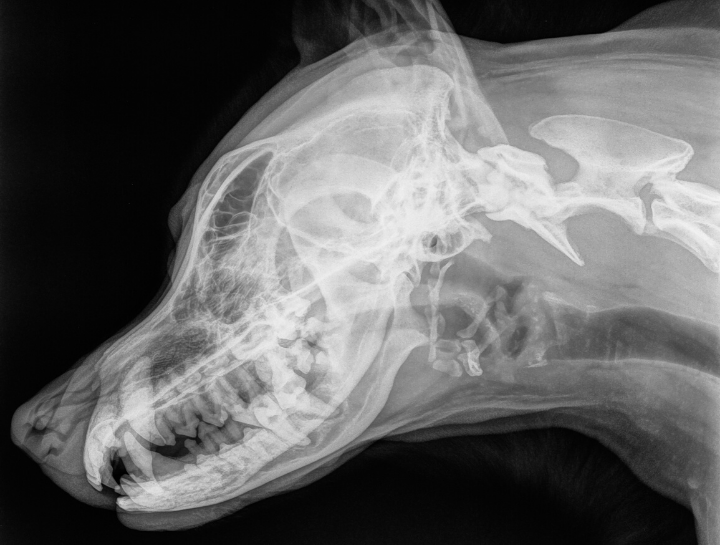

Digital Dental Radiology